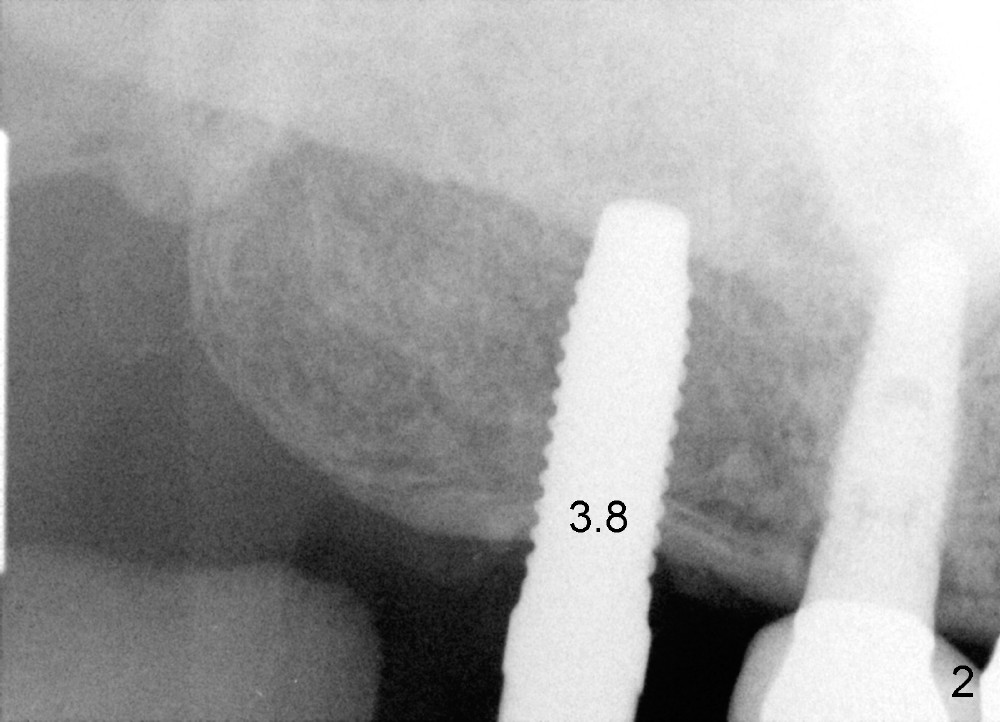

Analysis of preop PA suggests that the density of the cancellous bone is low at the site of the tooth #2. It is confirmed when a 2 mm pilot drill is used to initiate osteotomy. There is no drilling resistance once the pilot drill penetrates the cortex. A parallel pin is inserted for trajectory (Fig.1: P; 8 mm deep). The osteotomy is slightly moved distally with Lindermann bur and enlarged by inserting Bone Expanders from 2.6 to 3.8 mm at the depth of 12 mm (Fig.2). The osteotomy is then intended to move mesially and the depth is increased to 14 mm. Finally a 5.3x14 mm submerged implant is placed with insertion torque ~ 40 Ncm (Fig.3). The implant looks to have been tightly engaged into the bone (Fig.4). In one word, minimal bone removal is required for implant placement in the soft bone, particularly in the maxillary posterior region. A 8.2 mm healing abutment is placed; the flaps are closed by Chromic gut suture and perio glue (Fig.5). The wound heals normally 1 week postop (Fig.6). Fig.7 shows X-ray 3 months postop (H: healing abutment). Soft tissue looks healthy 4 months postop before (Fig.8) and after (Fig.9) removal of the healing abutment for restoration. There is no bone loss 7 months post cementation and 11 months postop (Fig.10 C: crown). It appears that bone expansion prevents bone resorption. There is no bone resorption 1 year 9 months post cementation. The implant is functioning 3 years 9 months post cementation (Fig.11).